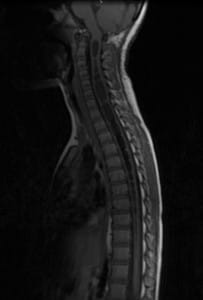

Imatges: Avant i després de la Sección del Filum Terminale

Què succeeix amb el quist de la siringomielia?

A la siringomielia la secció del filum deté la malaltia, el quist resultat de la mort cel·lular queda igual, però pot desaparèixer quan espontàniament s´obre a l´espai que envolta la medul·la espinal o ho fa cap al centre d´ella on existeix un conducte, el conducte ependimario, que comunica el centre de la medul·la amb les cavitats cerebrals. Els símptomes d´aquesta malaltia es produeixen per la mort cel·lular i l´efecte tumor del quist. La secció del filum fa dos efectes beneficiosos: deté la mort cel·lular deguda a la tracció de la medul·la i disminueix l´efecte tumor del quist al relaxar la medul·la espinal.